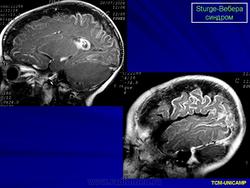

Магнитная резонансная томография пациента с болезнью Штурге - Вебера

Рентгенологически можно обнаружить обызвествление в затылочных и теменных отделах мозга. При ПЭГ у большинства больных отмечаются атрофия вещества мозга, расширение субарахноидальных щелей на конвекситальной поверхности и расширение полостей желудочков мозга.

Диагноз синдрома Стерджа - Вебера не представляет трудностей. Наличие корковых обызвествлений можно выявить при рентгенографии. Характерные тени располагаются в виде двойных контуров, повторяющих извилины пораженных долей мозга. Компьютерная томография выявляет более обширные области обызвествления, чем это видно при обычной рентгенографии.

Магнитная резонансная томография пациента с болезнью Штурге - Вебера